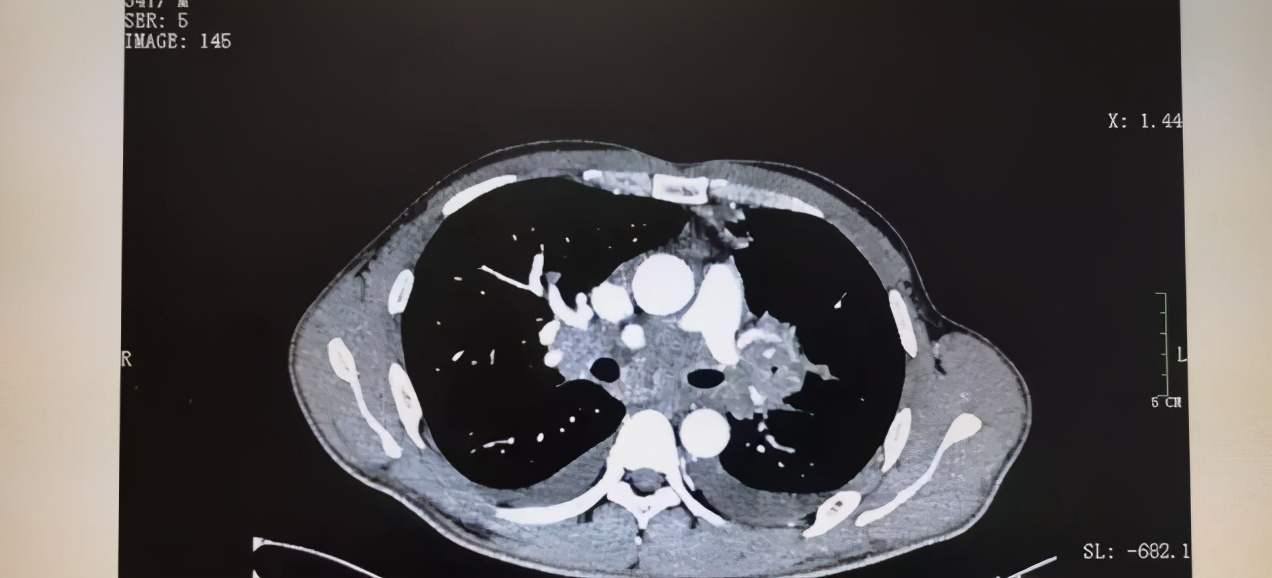

治疗几次后,CT显示转移病灶竟消失了,等到第11次后,原发病灶也消失,效果显著。出院后,张伟身体状况日益见好,8月随访期间增重40斤,这项治疗新方案让张伟重获新生。

(张伟肿瘤治疗后的CT,图源郑州人民医院)